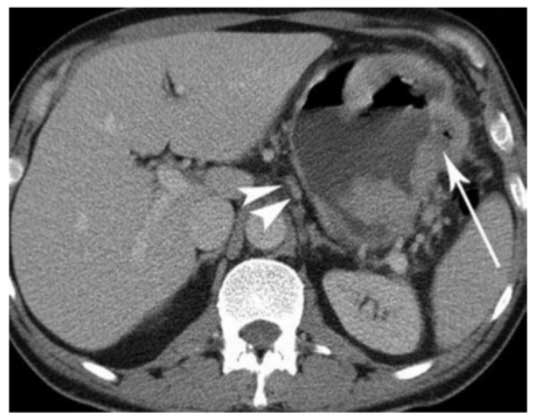

Рак Желудка Симптомы Фото

Рак Желудка Симптомы Фото 111 фото